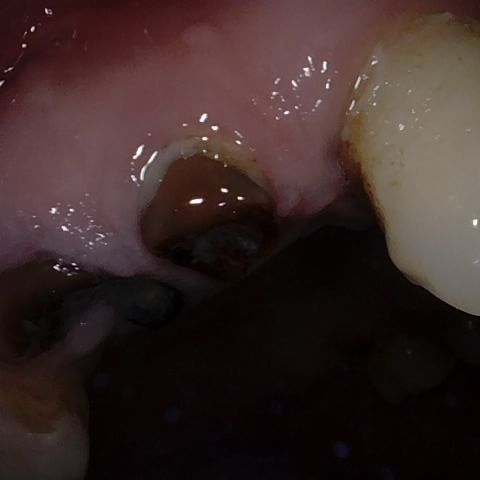

Annotated as "Good"